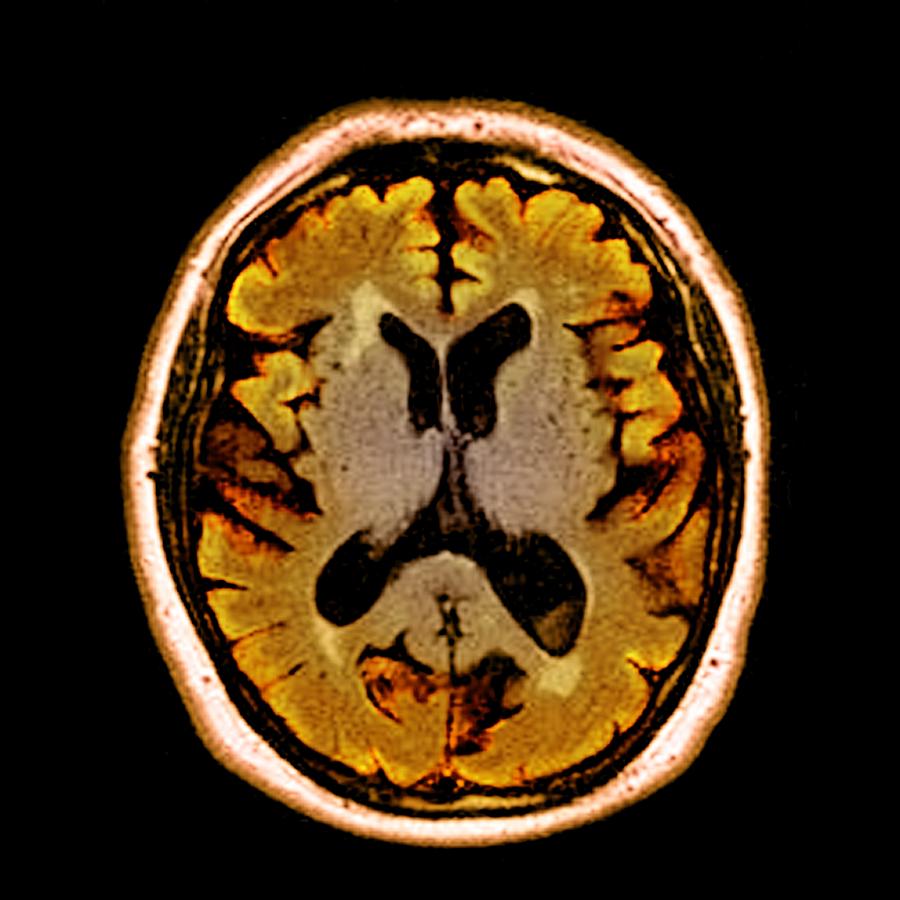

MRI Brain Dementia Stock Image. Image Of Science, Medicines - 105443423

mri gehirn demenz dementia

mri dementia brain atrophy preview